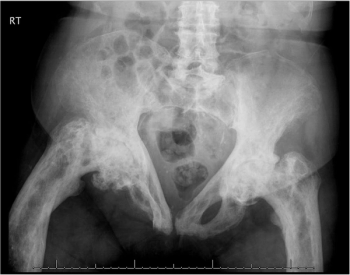

Oral etidronate, IV pamidronate, and then zoledronate caused bone markers to normalize in this 80-year-old woman-temporarily. What’s going on? Answer this and questions on 3 other topics in this week’s quiz.